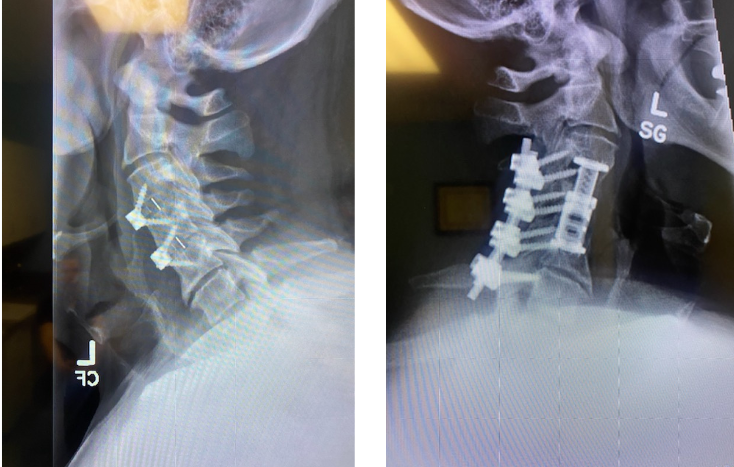

Javier's spine before and after treatment from Dr. Verma

Javier's spine before (left) and after (after) treatment from Dr. Verma

“We created an incision in his neck to reach the faulty implants,” said Dr. Verma. “We drilled into the bone, took out his old implants and put in a new plastic cage and screws to take pressure off the nerves in his neck.”